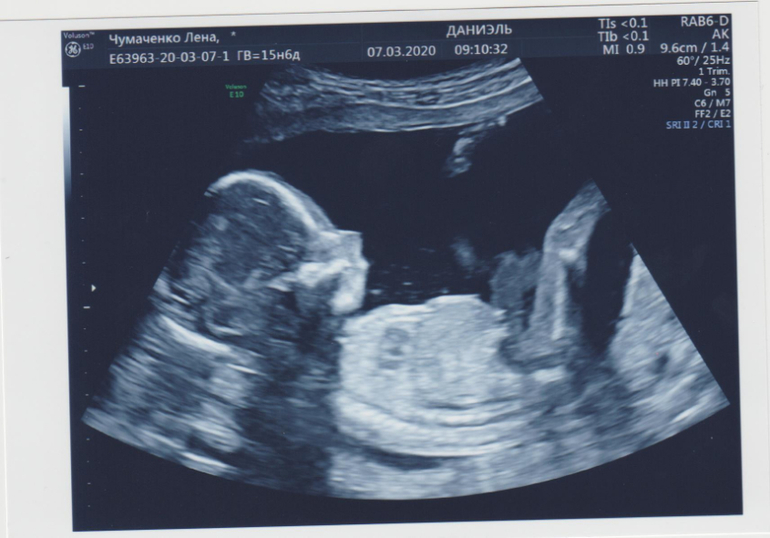

Узи 15.6

УЗИ, КТГ, доплерПо акушерскому 15.6, ктр 16.6

Мальчик! 164 грамма)

Вот в такой позе мы спим)

Я 3д не собиралась делать и даже не обсуждалось, это врач, когда увидела как он спит, врубила быстренько и сфоткала)))

Мне, то, что пацан, сказали еще в 12 недель, потом в 14, сегодня уже наверняка бубенчики показал, после того как разбудился:) Вот он отбивался, бедолага)))